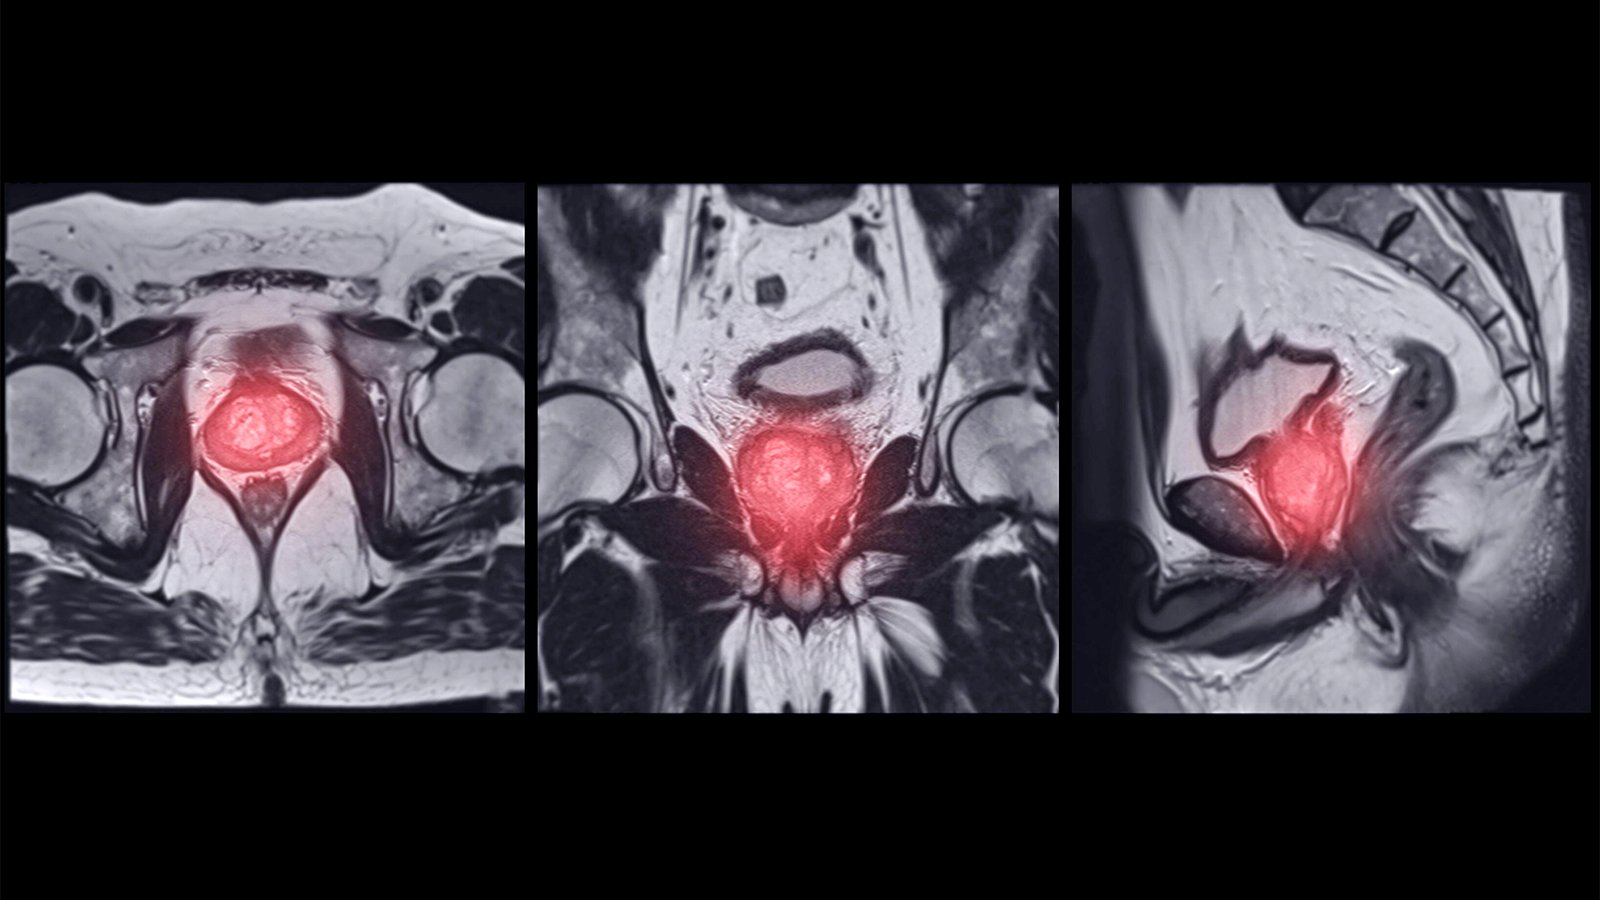

(MedPage Today) — Despite technologic advances and guideline recommendations, prostate MRI still lacks the accuracy to replace biopsies in active surveillance, data on almost 2,000 patients suggested.

MRI had a 75% negative predictive value …